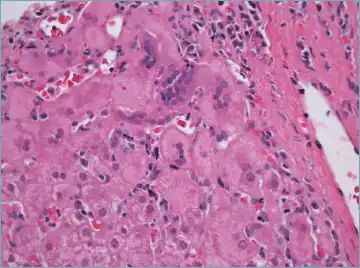

Micrograph showing a lymphoplasmacytic interface hepatitis—the characteristic finding of autoimmune hepatitis. Liver biopsy. H&E stain.

Histological features supportive of a diagnosis of autoimmune hepatitis include:[10]

• A mixed inflammatory infiltrate centered on the portal tract

• The inflammatory infiltrate may breach the interface between the portal tract and liver parenchyma: so-called interface hepatitis

• The most numerous cell in the infiltrate is the CD4-positive T cell.

• Plasma cells may be present within the infiltrate. These are predominantly IgG-secreting.

• Eosinophils may be present within the infiltrate.

• Emperipolesis, where there is penetration of one cell through another, within the inflammatory infiltrate

• Varying degrees of necrosis of periportal hepatocytes.

• In more severe cases, necrosis may become confluent with necrotic bridges forming between central veins.

• Hepatocyte apoptosis manifest as acidophils or apoptotic bodies.

• Rosettes of regenerating hepatocytes.

• Any degree of fibrosis from none to advanced cirrhosis

• Biliary inflammation without destruction of biliary epithelial cells in a minority of cases.